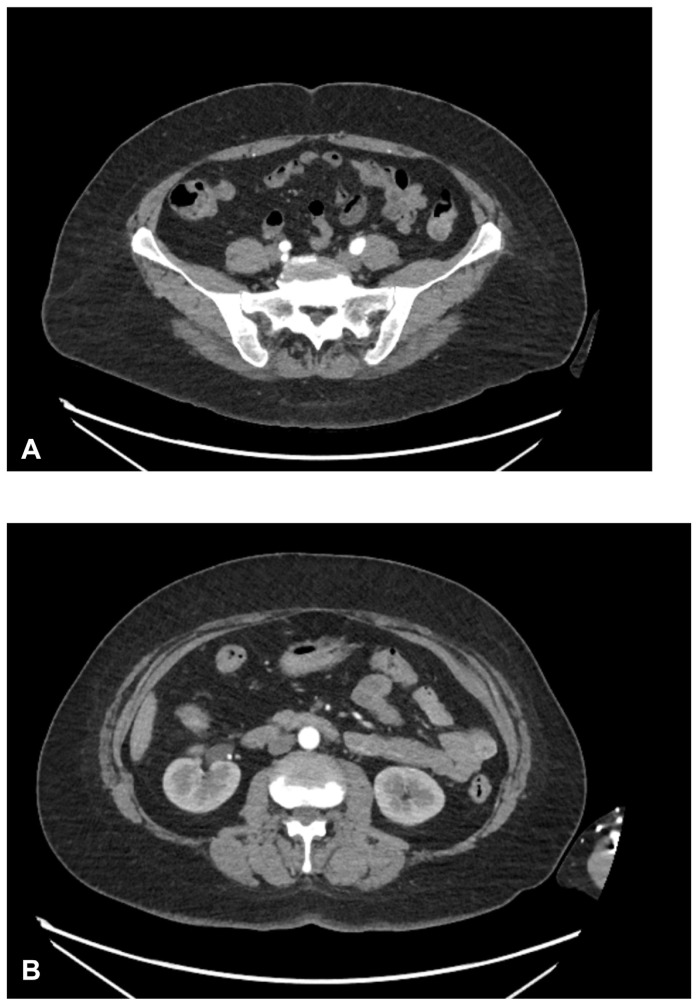

Background: Colonic varices (CV) remain an extremely rare condition, the usual cause of which is portal hypertension due to liver disease, chronic pancreatitis or malignancy. Here we present a case of familial idiopathic CV in a middle-aged female, complicated by a polyp removal during colonoscopy.

Case presentation: A 57-year-old female with a past medical history of 5 months of melena, polyps and hemorrhoids diagnosed with idiopathic CV during diagnostic colonoscopy. She had no prior history of liver disease, pancreatic disease, non-steroidal anti-inflammatory drugs (NSAID) use, or blood thinner use. She was later found to have a family history of the condition.